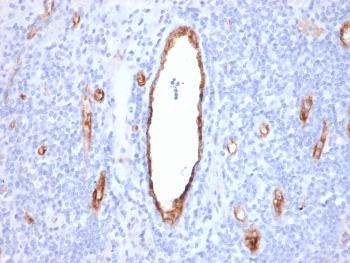

Fig. 1: Formalin-fixed, paraffin-embedded human Pancreatic Carcinoma stained with MRP3 Mouse Monoclonal Antibody (ABCC3/2971).

Immunohistochemistry (Formalin-fixed) (1-2ug/ml for 30 minutes at RT)(Staining of formalin-fixed tissues requires heating tissue sections in 10mM Tris with 1mM EDTA, pH 9.0, for 45 min at 95°C followed by cooling at RT for 20 minutes)